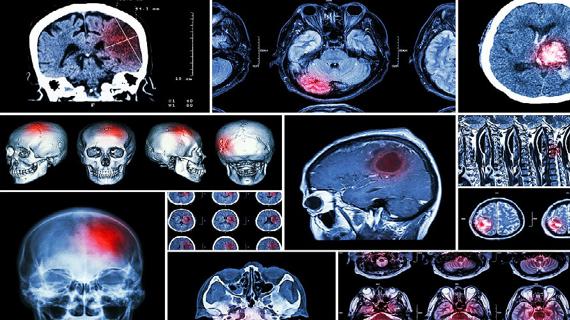

Инсульт головного мозга — Симптомы и методы лечения инсульта, советы врачей

Инсульт головного мозга - как распознать и не допустить. Инсульт головного мозга - это заболевание сосудов, которое развивается внезапно...

Головной мозг — Заболевания мозга и нервной системы